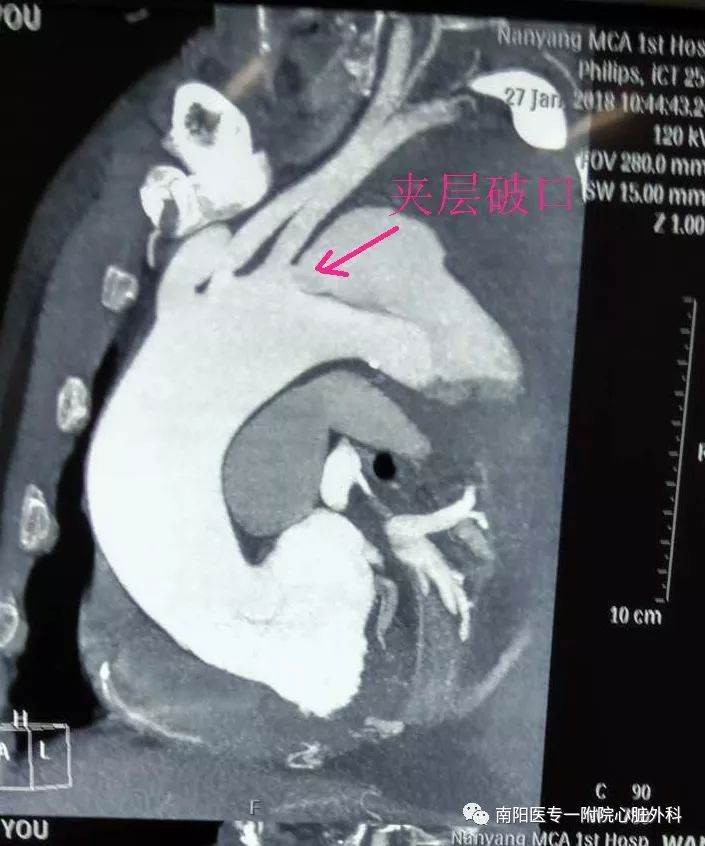

立即行CTA,明确诊断为Stanford B 型主动脉夹层,破口位于左锁骨下动脉根部,并且主动脉弓部明显增宽,左侧胸腔大量积液。此种情况非常危险,为主动脉夹层濒临破裂的征象,随时有发生破裂死亡的可能。